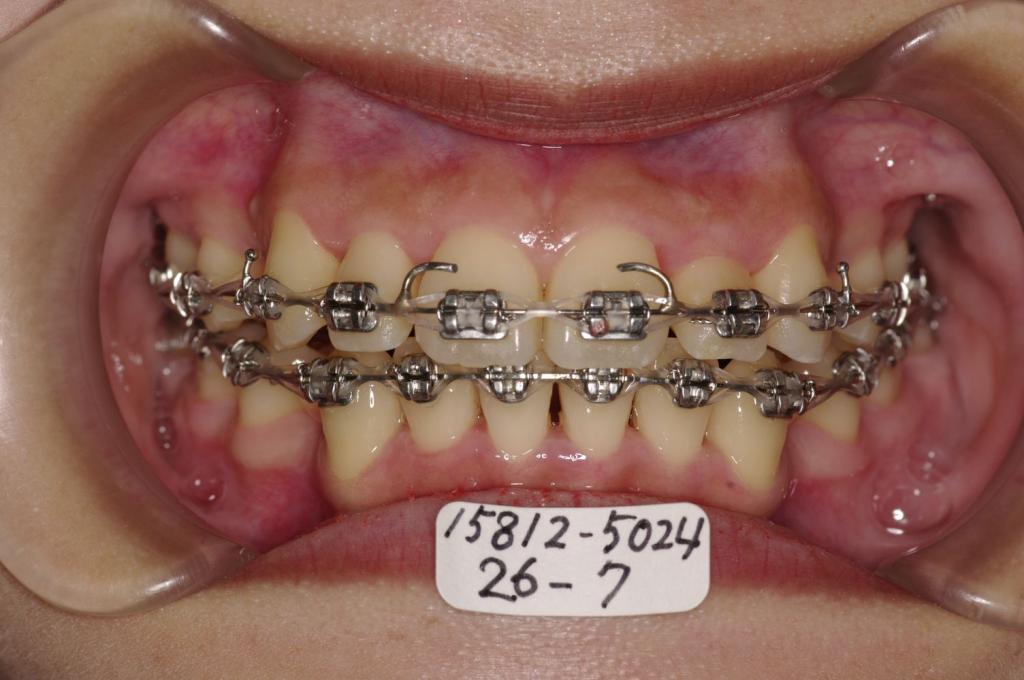

装置の種類及び治療法 診断:叢生

治療方法および装置:マルチブラケット装置

High pull J-hook headgear

抜歯:右上4 /左上4

右下84 /左下4

欠損歯:右上8 /左上8

右下 /左下8

治療期間:22ヶ月

装置写真

治療前

歯並び・咬み合わせ・八重歯・乱杭歯の矯正治療前口内写真NO.1209